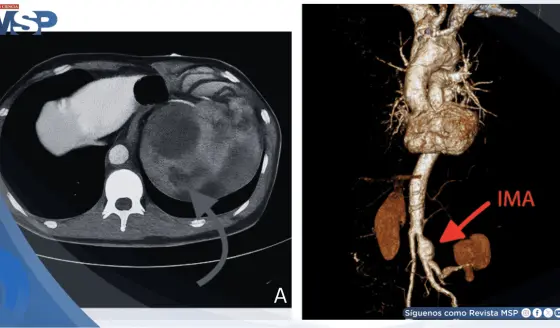

Aneurisma roto simuló infección urinaria: Dolor lumbar e hidronefrosis confundieron el diagnóstico